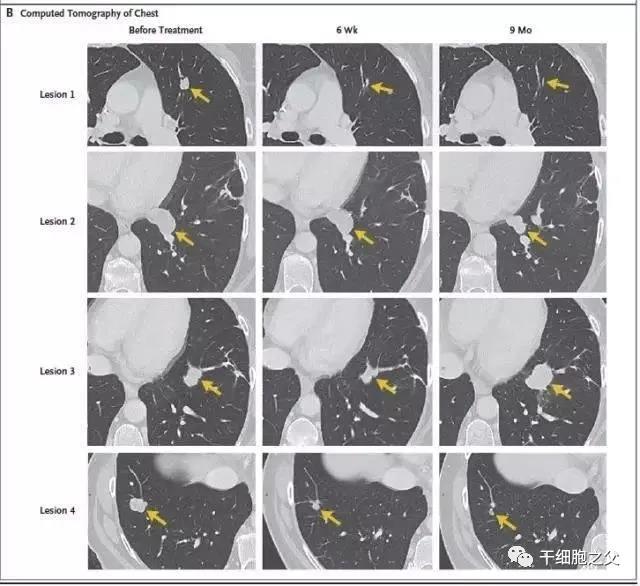

此后,Celine Ryan接受了细胞的回输。40天后,检查发现她体内的病灶已经在缩小,又过了9个月,她体内原先的7个病灶完全消失。如今Celine Ryan仍然健康,身体没有任何复发的迹象,医生们惊呼这是新型免疫疗法带来的又一例奇迹。

Celine Ryan复查时的CT扫描